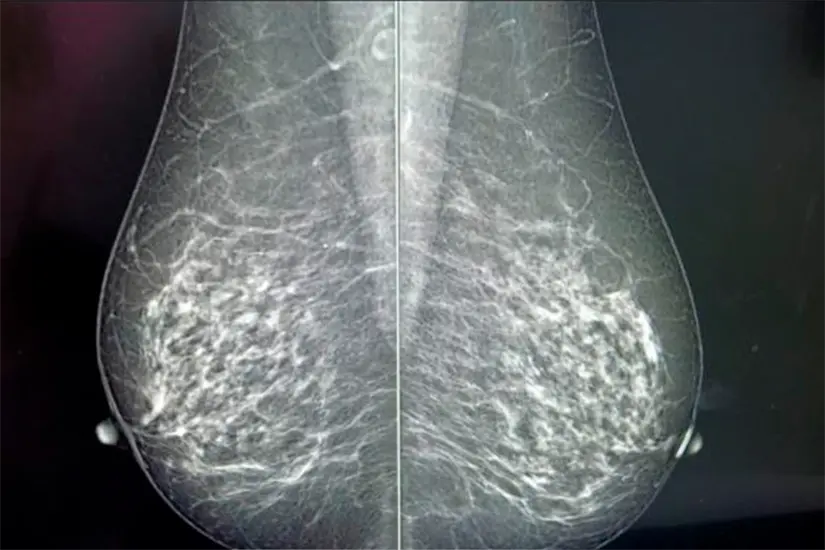

La mastografía es un estudio radiológico capaz de detectar principios de cáncer de mama cuando aún no se logra palpar el tumor; con ello,se busca detectar cambios o anormalidades en los tejidos del seno, pequeños nódulos o masas que no los puede sentir una persona y que con el tiempo pueden convertirse en problemas.

El estudio consiste en tomar dos radiografías de cada mama: de los lados y de arriba hacia abajo; este procedimiento tarda alrededor de 15 minutos y causa molestias que son tolerables, ya que se requiere comprimir el seno.